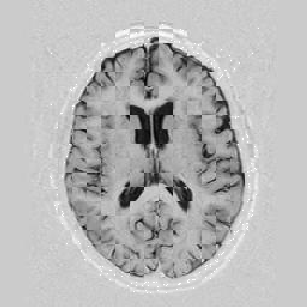

I later attempted 10 iterations at level 2, then 2 iterations at level 1, and 1 iteration at the finest level. Visual results can be seen in Figure [*].

Figure: Multi-scale NRR. From left to right, top then bottom: before NRR; after 10 iterations of NRR at level 2; after another 2 iterations of NRR at level 1; after 1 iteration at level 0.